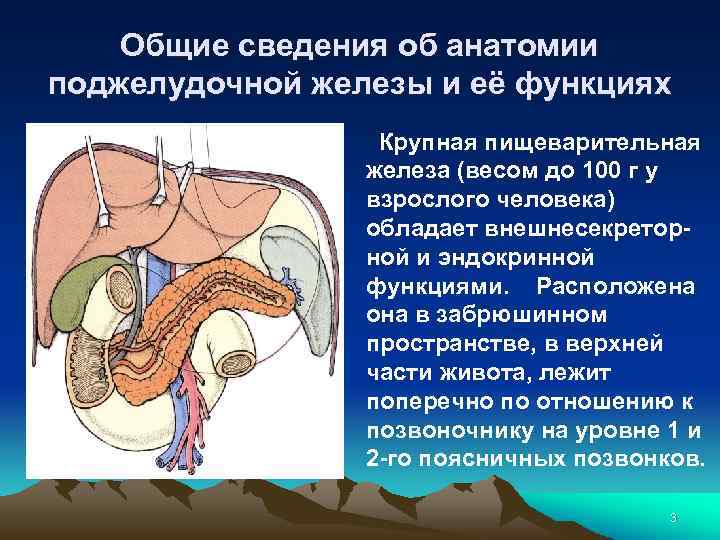

Общие сведения об анатомии поджелудочной железы и её функциях Крупная пищеварительная железа (весом до 100 г у взрослого человека) обладает внешнесекреторной и эндокринной функциями. Расположена она в забрюшинном пространстве, в верхней части живота, лежит поперечно по отношению к позвоночнику на уровне 1 и 2 -го поясничных позвонков. 3

Общие сведения об анатомии поджелудочной железы и её функциях Ткань поджелудочной железы имеет альвеолярнотрубчатое строение, она разделена соединительной тканью на дольки. В последних расположены ацинусы - клетки вырабатывающие поджелудочный сок. Протоки долек сливаются в более крупные и, наконец, в общий выводной проток. 4